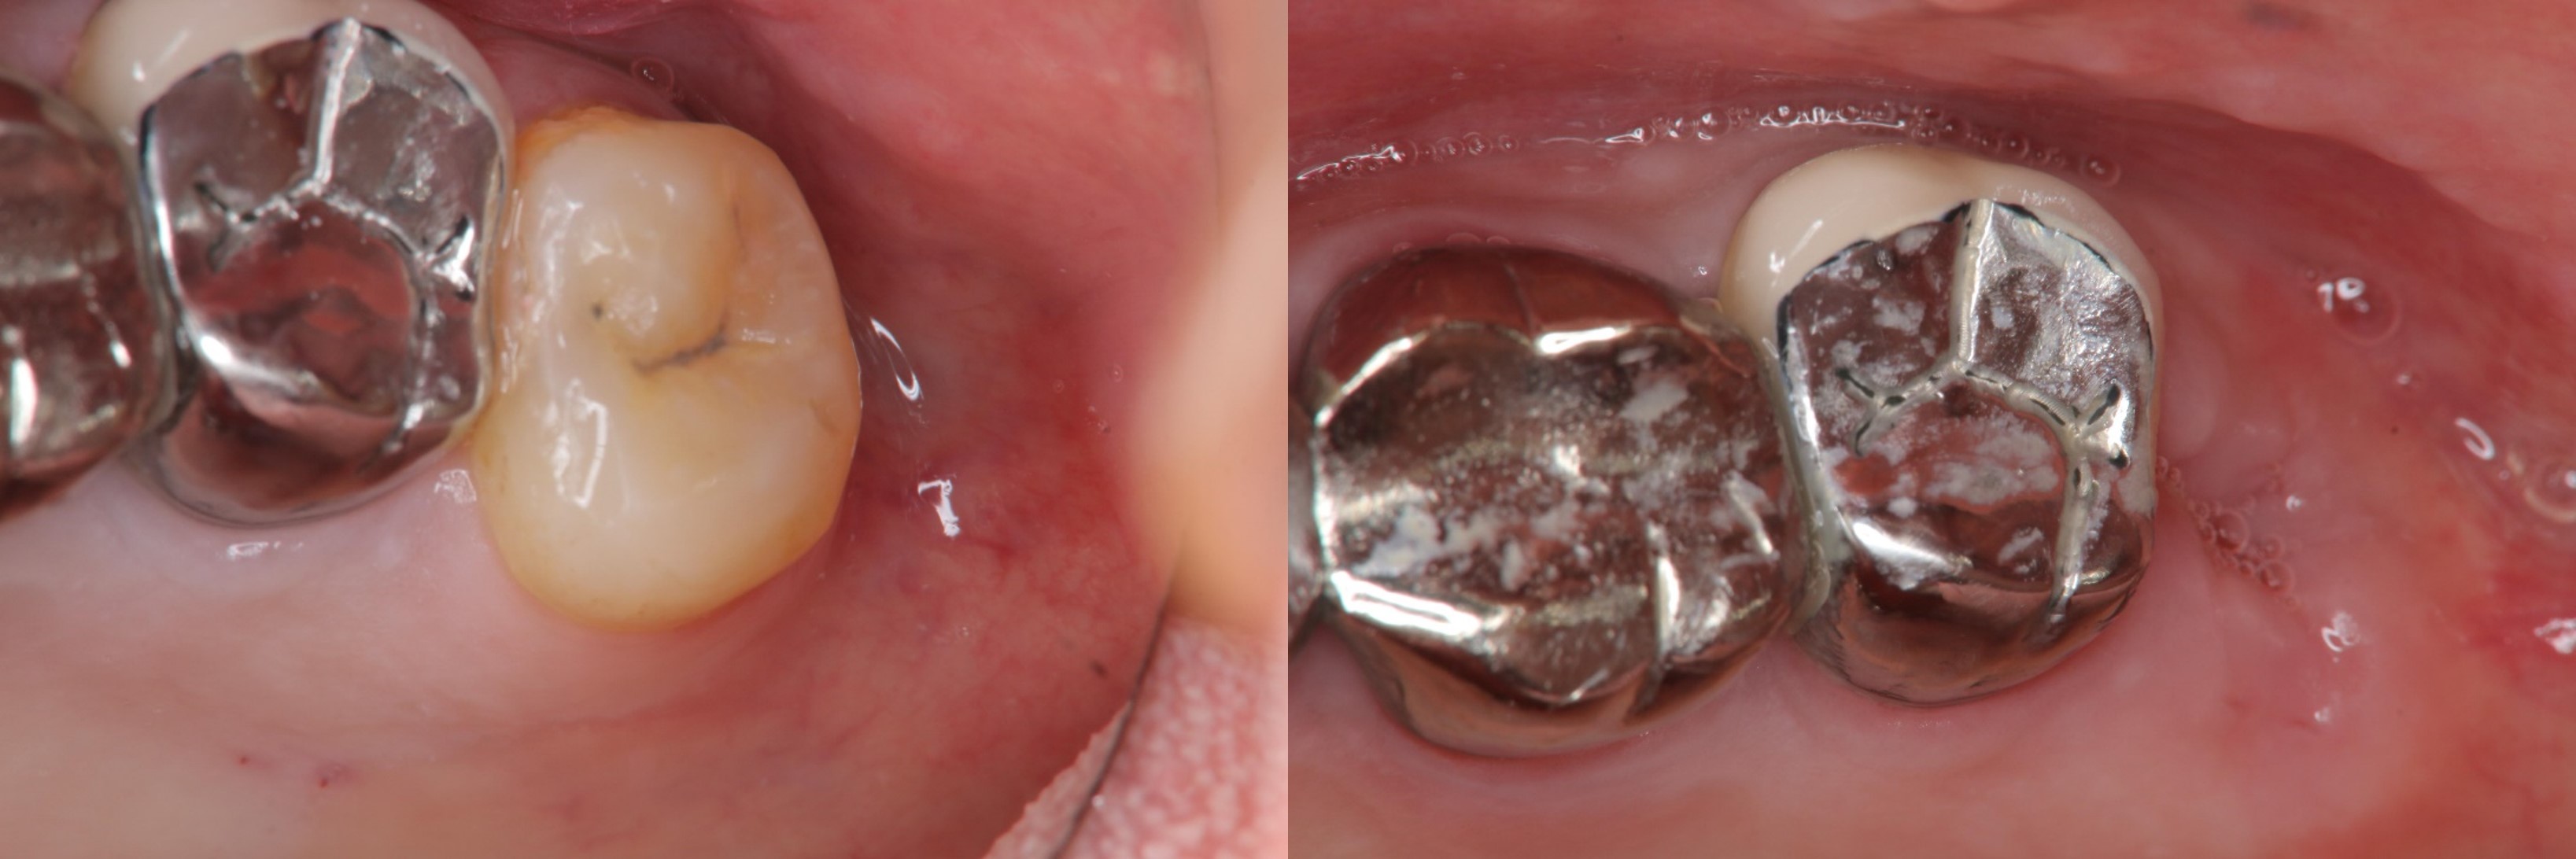

牙髓-牙周-膺復合併症-磨耗-#27、37

根管治療

牙髓/牙周/膺復合併症

牙周-膺復合併治療-牙齦下蛀牙-#37